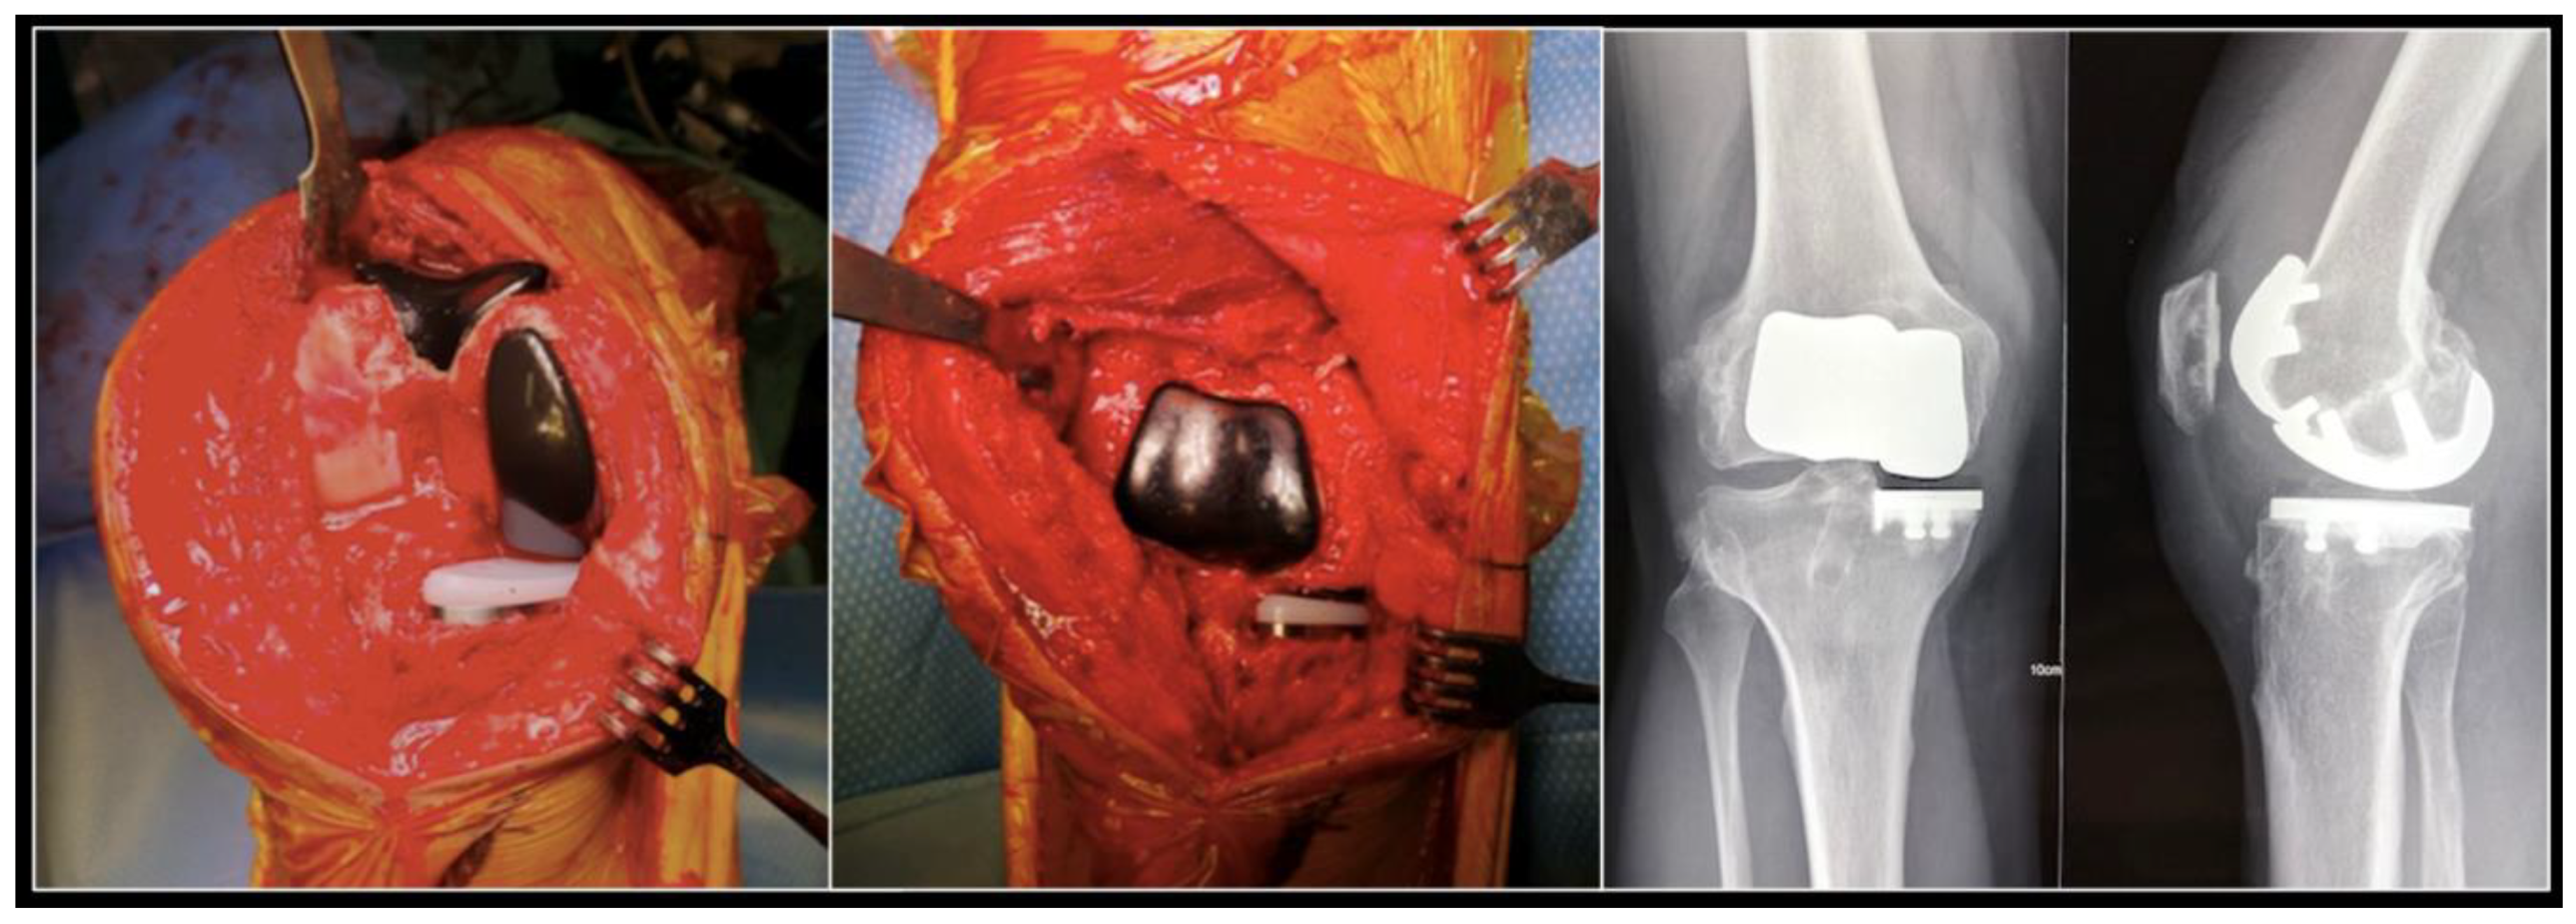

In some cases, if the patient is young and active with bicompartmental osteoarthritis, there may be an indication for two partial knee replacements (usually a medial unicompartmental arthroplasty and a patellofemoral replacement) (Figure 5). Despite long-standing support for this surgery, in particular from Philippe Cartier, it is technically challenging. The Navio® system can be used to predict and adjust the relative position of the two implants, making this uncommon procedure more consistent.

Figure 5.

Per operative pictures and radiographs of a medial unicompartmental arthroplasty associated to a patellofemoral replacement in a young and active patient.